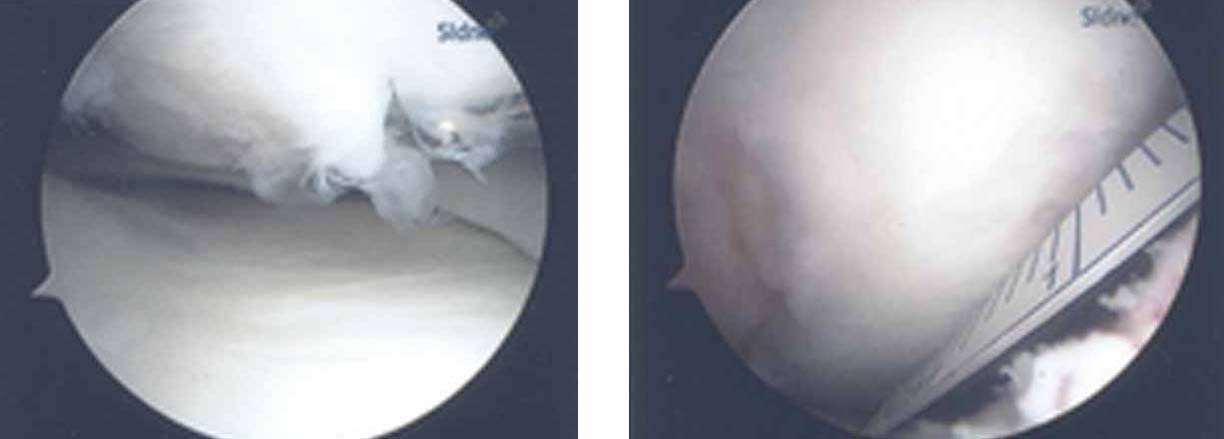

3.The arthroscopic views confirm a full thickness cartilage defect in the medial femoral condyle. The lesion is measured with a cut plastic ruler on the image on the right.

4.Due to the location of the lesion, an open mosaicplasty with one plug is selected as our treatment choice. The harvesting tool is placed within the lesion removing the plug with the damaged cartilage. On the image on the right, the inside of the recipient site is inspected with the arthroscope.

5.In the image to the left, the donor plug (left plug) and recipient plug (right plug) are placed next to each other demonstrating the degree of damage in the recipient site. The image on the right shows the donor plug after being placed flush with the recipient cartilage into the recipient site.